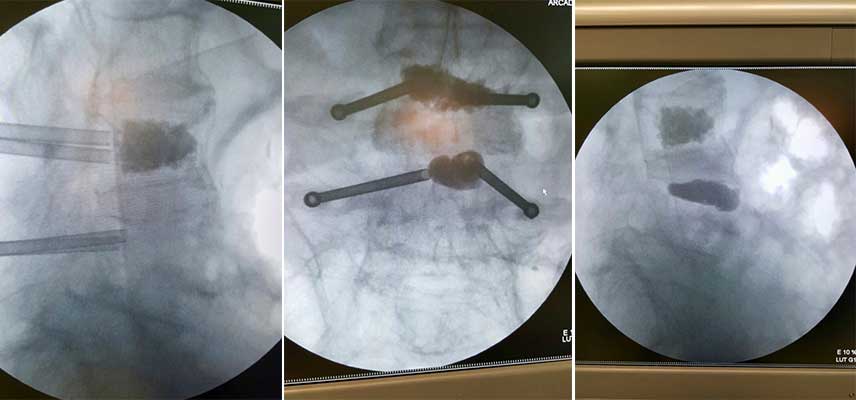

We use X-ray guidance to insert a balloon through a needle into the vertebral fracture, which extends upwards realigning the bone and creating a cavity within the vertebra. The fractured vertebrae are strengthened by the injection of special hardening material into the cavity when the balloon is removed. The surgical incision is about 0.5 cm.

With the digital technology of 3D navigation, X-ray and neuroscience available to us and with our extensive experience as surgeons (we have been applying it since 2004) the probability of complications due to surgery is substantially nonexistent. Kyphoplasty is a new, safe method for the treatment of osteoporotic fractures and other serious spinal problems.